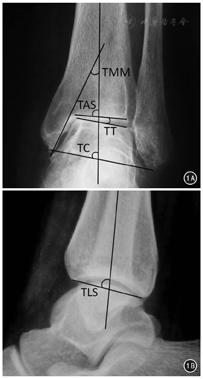

(1)传统踝上截骨术:取踝关节前内侧切口,显露踝关节前内侧间隙和胫骨远端前内侧骨面,截骨线位于内踝尖上4~5 cm,其外侧多位于下胫腓联合上方。克氏针术中定位,用摆锯由内向外平行于胫骨远端关节面,截断内侧、前侧及后侧皮质,保留外侧皮质。(2)踝上斜形截骨术:取踝关节前内侧或胫骨远端内侧切口,显露胫骨远端前内侧骨面,截骨线位于内踝尖上4~5 cm,截骨线外侧多位于下胫腓联合水平,通过克氏针术中定位,用摆锯由内向外截断内侧、前侧及后侧皮质,保留外侧皮质。(3)关节内截骨术(Myerson截骨术)[16]:取踝关节前内侧或胫骨远端内侧切口,显露胫骨远端前内侧骨面,截骨线位于内踝尖上4~5 cm,截骨线外侧多位于胫骨远端关节内畸形顶点位置,通过克氏针术中定位,并平行关节面预置2~3枚1.0 mm克氏针保护关节面,避免截骨与撑开时造成关节内骨折移位;用摆锯截断内侧、前侧及后侧皮质。

撑开截骨间隙,采用自体骨(7例)或同种异体骨(47例)填充截骨间隙;术中透视确定和调整至矫形满意后,行胫骨远端内侧接骨板固定。

内侧软组织松解:通过前内侧切口,用尖刀松解三角韧带浅层前束及部分三角韧带深层,避免完全切断。踝关节外侧副韧带修复:采用改良Brostrom手术,通过带线锚钉,用踝关节伸肌下支持带加强修复距腓前韧带结构。内侧外固定架牵开:对于术中持续存在距骨倾斜的患者,透视下于距骨打入1枚骨钉,2枚骨钉分别打入胫骨和跟骨,连接并固定外架,通过距骨骨针进一步撑开内侧间隙,矫正距骨倾斜角。

末次随访时,AOFAS评分较术前提高,AOS疼痛评分与功能评分较术前降低,差异均有统计学意义(P值均<0.01)。32例(59.3%)患者Takakura分期较术前改善,即分期有下降;17例(31.4%)无改善,即分期无变化;5例(9.3%)有进展,即分期有增加;手术前后比较,差异均有统计学意义(P<0.01)。改良Takakara分期分别赋值后统计比较结果见表2。影像学测量评估,除TLS外均较术前有显著改善(P值均<0.01)。其中94%(16/17)术前TT>4°的患者术后关节面协调性得到恢复(TT≤4°)[8];78%(7/9)术前TT≥10°的患者术后关节面协调性得到恢复(TT≤4°)。见表2。典型病例见图2,图3,图4,图5。